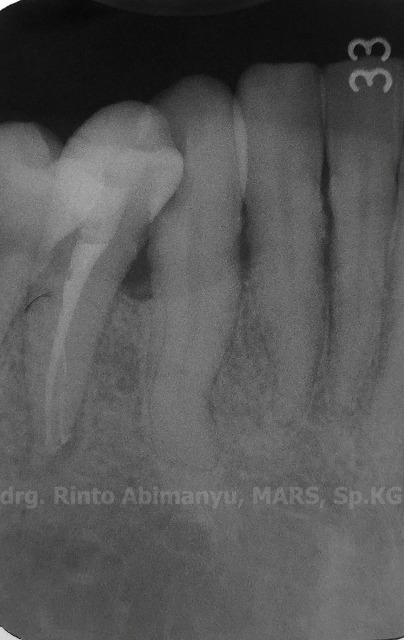

Radiografis gigi 43

Wah saluran akarnya agak “meliuk’ nih hehehe… Saya suka deg2an kalau mendapatkan saluran yang seperti ini, karena pengerjaannya harus hati2 dan sabar…

Setelah juga didapat kondisi yang lancar keluar masuk, dilakukan pengukuran panjang kerja menggunakan apex locator (Root ZX mini – Morita)… dan dilanjutkan dengan memuluskan jalur luncur menggunakan ProGlider (Dentsply)… Pada kasus ditemukan saluran akar yang agak berliuk seperti ini, tahap penjajakan dari no.8 sampai pemulusan jalur dengan ProGlider sangat penting sebelum kita memulai preparasi saluran akarnya, agar terhindar dari masalah seperti ledge, jarum patah, instrumen tertahan tidak bisa masuk lebih dalam dan sebagainya…

Pada kasus ini yang bisa dijadikan catatan adalah : dalam menghadapi saluran akar yang agak ada belok2 usahakan sabar dalam penjajakan awal, pastikan pada saat penjajakan tersebut file yang digunakan sudah dapat keluar masuk tanpa hambatan sehingga akan memudahkan file rotary yang kita gunakan untuk meluncur di saluran akar itu…